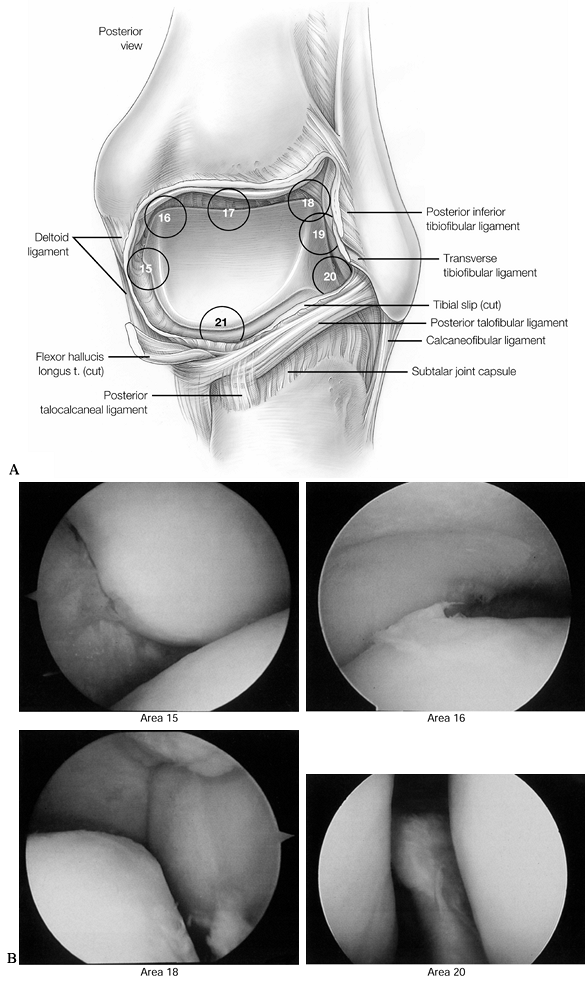

| Figure 93.8. A 7-point posterior examination as viewed from the posterolateral portal. A: The posterior examination begins along the posterior medial malleolus and is then rotated clockwise to complete the exam in the posterior recess. (See COLOR FIG. 93.8B). B: Arthroscopic views of points 15, 16, 18, and 20. (Copyright 1996 by Lippincott-Raven Publishers. From Ferkel RD. Arthroscopic Surgery: The Foot and Ankle. Philadelphia: Lippincott-Raven Publishers, 1996:114, with permission. Illustration by Susan Brust.) |